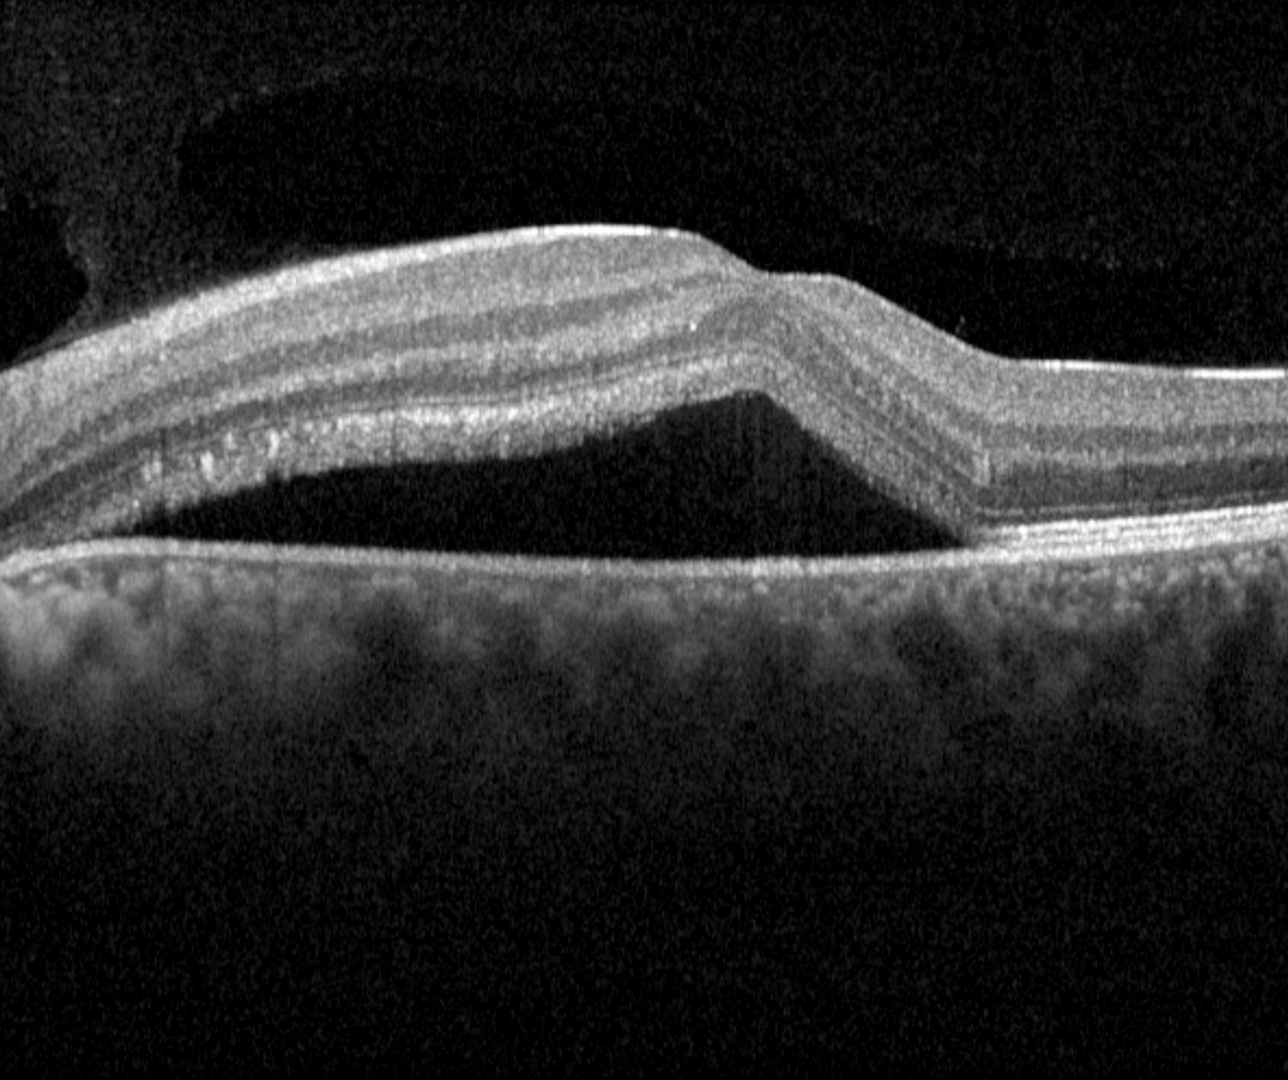

OCT shows a well defined, dome-shaped, serous retinal detachment usually associated with a serous PED. The retinal layers are otherwise undisturbed in acute presentations, however, in cases of persistent subretinal fluid, elongation of the photoreceptor outer segments, subretinal fibrin, and subretinal yellowish dots can occur.